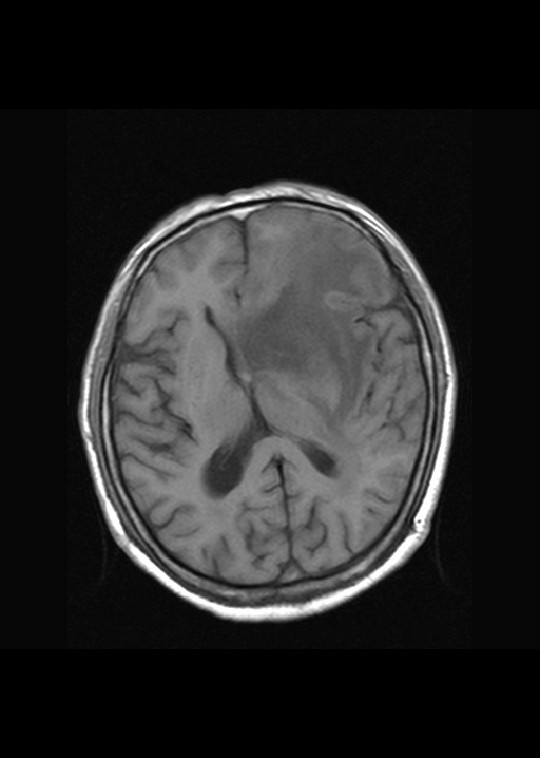

左侧基底节区病灶t1wi呈不均匀稍低信号,t2wi呈稍高信号,周围伴有水肿。增强扫描呈均匀团块样或者抱拳样明显强化,相邻的柔脑膜亦见线样强化。首先考虑淋巴瘤。可惜没有ct平扫,如果ct平扫病灶呈高密度,那么更支持pcnsl的诊断。

左侧基底节区长t1长t2异常团块状信号,增强呈明显均一强化,水肿明显,挤压侧脑室前脚,本人考虑为胶质瘤可能性大。

左侧基底节区病灶t1wi呈不均匀稍低信号,t2wi呈稍高信号,周围伴有水肿。增强扫描呈均匀团块样或者抱拳样明显强化,首先考虑淋巴瘤。

淋巴瘤,信号及强化方式较典型。灶周方广泛水肿相对较少见。长见识了。